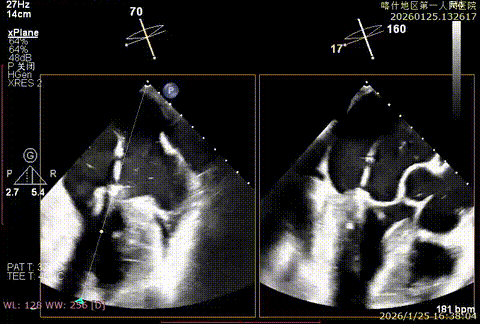

该例患者为DMR,脱垂区域较宽,术前制定手术策略:使用2把XTR先于患者外侧交界至1区部位进行钳夹。术中房间隔穿刺高度为4.0cm。成功穿刺后将SGC和XTR-CDS依次送入左心房,通过操控“M”旋钮调节SGC,使二尖瓣夹避开华法林脊,成功定位于2区正上方。在2区进行弹道测试成功后,进行Orientation调整。第一把于外侧交界区夹持,第二把于1区夹持,术中成功捕捞和夹持瓣叶后缓慢关紧夹臂,TEE检查见二尖瓣反流程度降低至1+,术后平均跨瓣压差3mmHg,手术顺利结束。

重度反流

SCG进入左房

3D enface进行Orientation调整

捕捞并夹持瓣叶

反流降低

第二枚XTR定位

Orientation调整

捕捞并夹持瓣叶,反流有效降低

组织桥稳定

术后平均跨瓣压差3mmHg